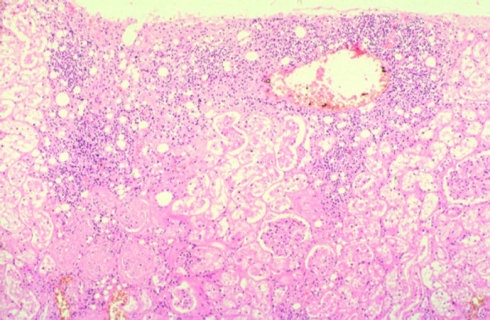

原发性腹膜炎临床上较少见,是指腹腔内无原发病灶,病原菌是经由血循、淋巴途径或女性生殖系等而感染腹腔所引起的腹膜炎。多见于体质衰弱,严重肝病患者或在抗病能力低下的情况下。

继发性腹膜炎是临床上最常见的急性腹膜炎,继发于腹腔内的脏器穿孔,脏器的损伤破裂,炎症和手术污染。